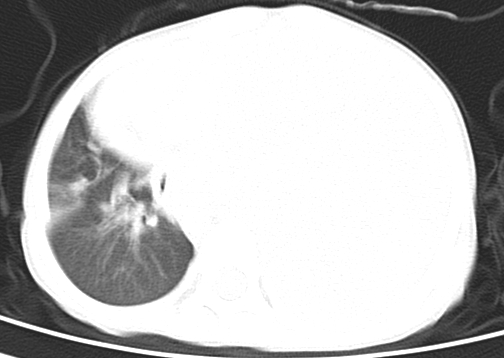

患儿 女 4岁,发热 咳嗽 胸透 考虑:左侧脓胸

左侧胸廓内见大量密实阴影,肺尖部尚有少量肺组织影,纵膈明显受压移位,肋骨未见明显受侵征象,虽然病人年龄较小,但如此大量的“积液”,还是要警惕,不同意一般感染,可结合穿刺脱落细胞学检查。

1)考虑左肺炎症感染。2)左侧大量胸腔积液。

1)考虑左肺炎症感染。2)未经穿刺只能定左侧大量胸腔积液。

左侧张力性大量胸腔积液压迫性肺不张、感染;建议治疗后复查。